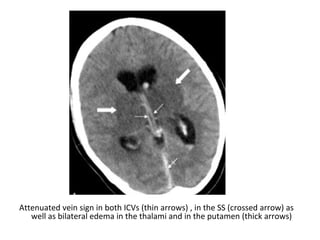

Attenuated vein sign in both ICVs (thin arrows), in the SS (crossed arrow)

Attenuated vein sign in both ICVs (thin arrows) , in the SS (crossed arrow) as

well as bilateral edema in the thalami and in the putamen (thick arrows)